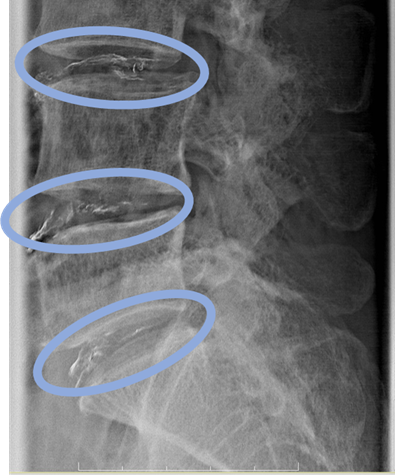

画像及び所見について

L1/2: 異常なし

L2/3: 軽度椎間板変性

L3/4: 椎間板変性、黄色靭帯肥厚、脊柱管狭窄症

L4/5: 椎間板変性

以上の事が画像上認められます。

・L3/4、4/5、5/S-椎間板変性、黄色靭帯肥厚、脊柱管狭窄症を認め、主症状の原因の可能性が高い。

DiscoGelを入れた後の画像になります。